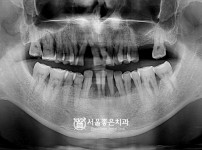

|  | 334 |  | 수면치료 + 보철치료, 뼈이식 임플란트 6개 - 네오 임플란트